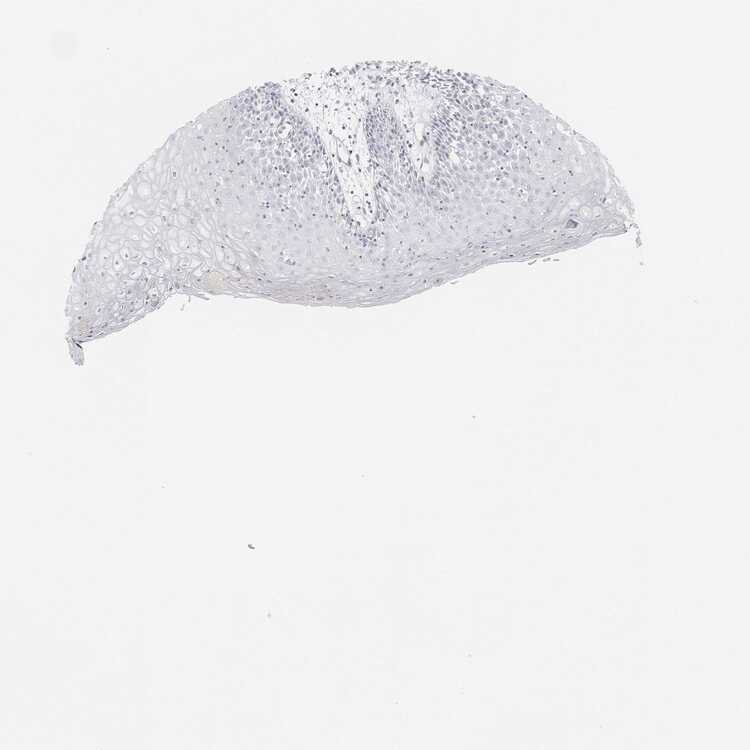

TISSUE PRIMARY DATA ORAL MUCOSA Show tissue menu

Oral mucosa

ORAL MUCOSA - Antibody stainingi

Antibody staining in the annotated cell types in the current human tissue is reported as not detected, low, medium, or high, based on conventional immunohistochemistry profiling in selected tissues. This score is based on the combination of the staining intensity and fraction of stained cells.

Each image is clickable and will lead to virtual microscopy that enables deeper exploration of all samples and also displays staining intensity scores, fraction scores and subcellular localization as well as patient and tissue information for each sample.

Squamous epithelial cells Not detectedNot detectedNot detectedNot detected